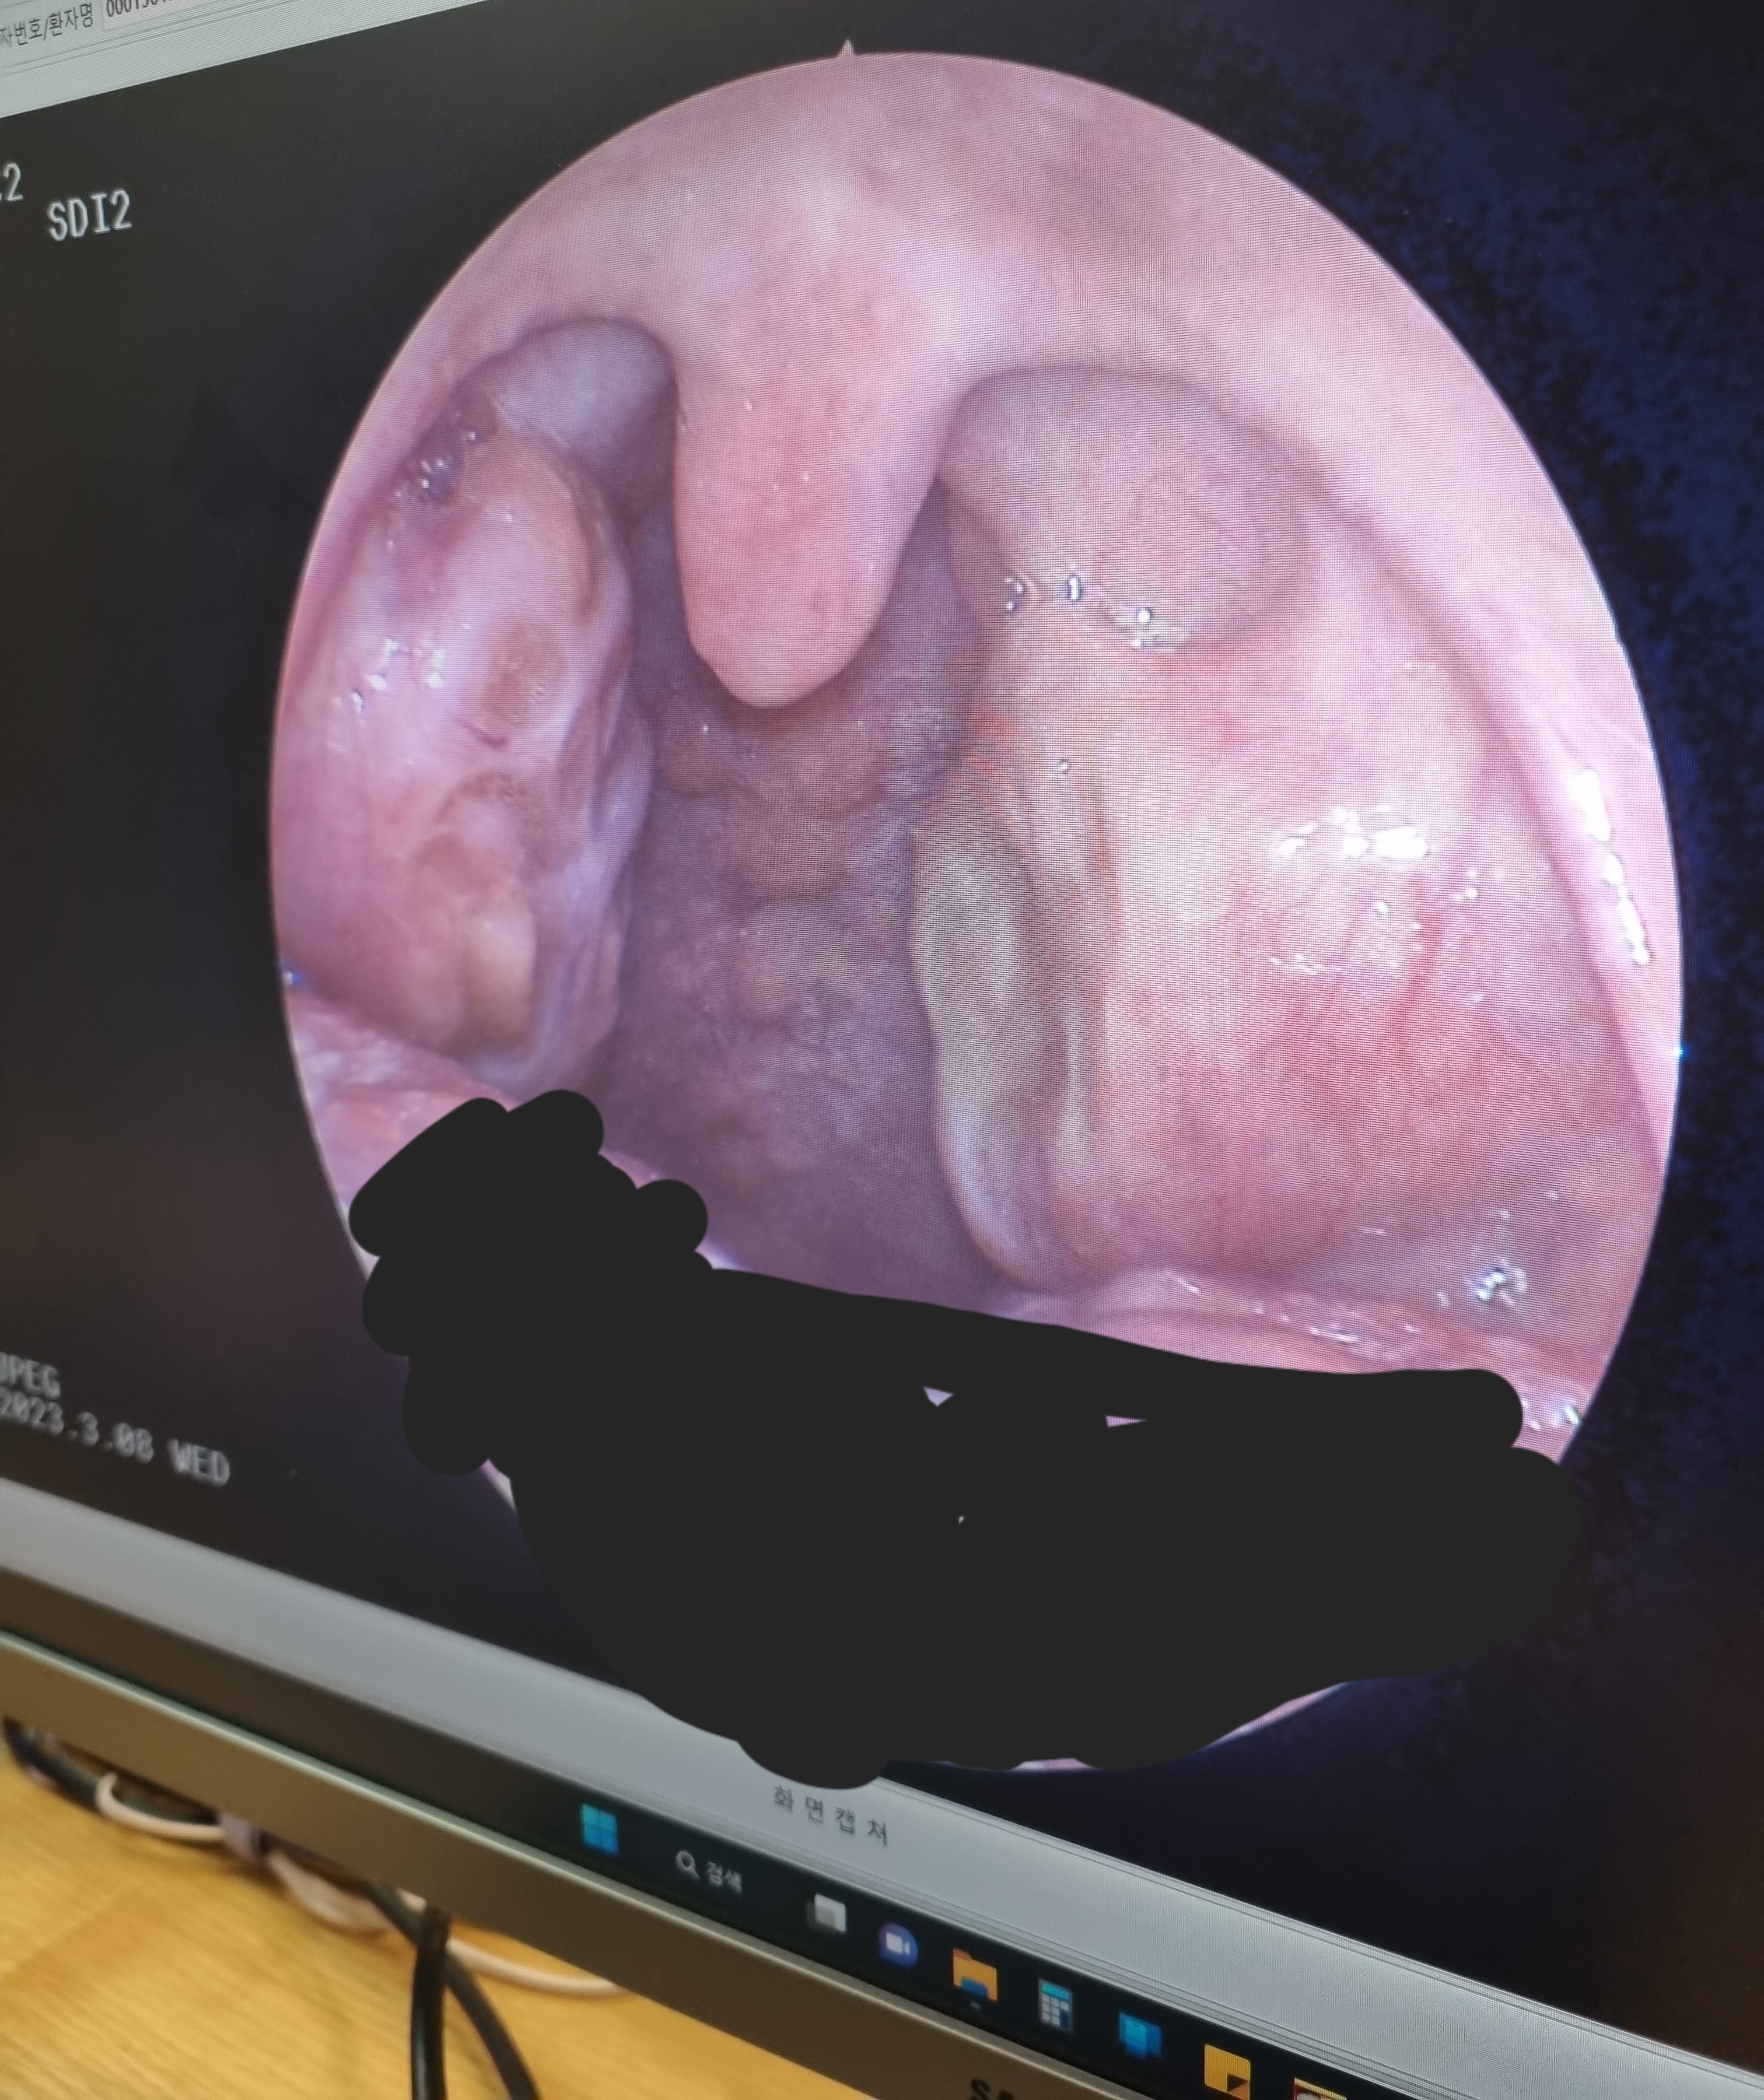

이건 이비인후과에서 찍어준건데 양 옆에 편도 크기 보여???

엄청나게 커서 나도 놀람